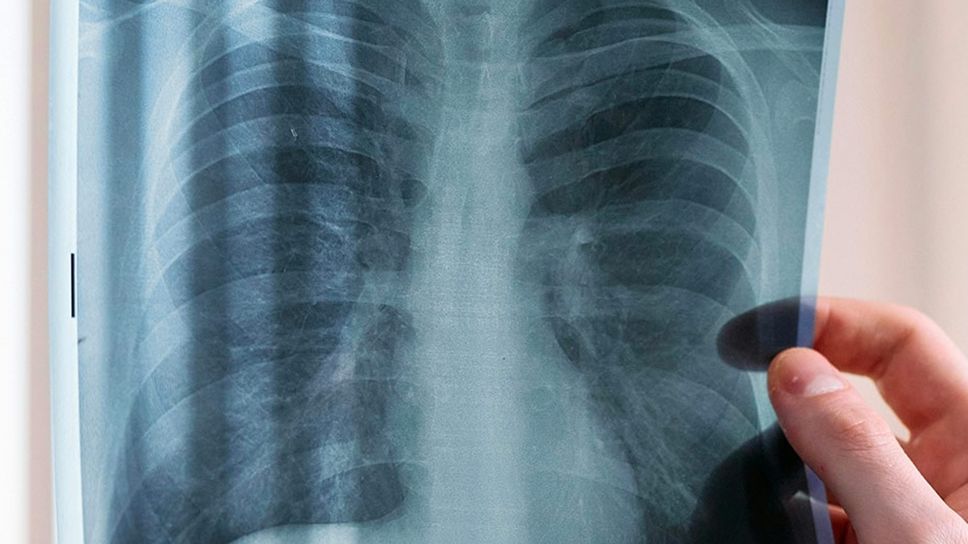

Respirare con fatica, avere una tosse secca persistente, sentire una stanchezza insolita anche per piccoli sforzi: possono sembrare segnali banali, ma in alcuni casi nascondono una patologia rara e insidiosa, la fibrosi polmonare progressiva (PPF). Si tratta di una condizione in cui il tessuto del polmone, per cause diverse, si indurisce e perde elasticità, compromettendo la capacità respiratoria e riducendo gradualmente la qualità di vita.

La PPF può manifestarsi come complicanza di malattie autoimmuni e reumatologiche – come artrite reumatoide e connettiviti – oppure come evoluzione di una fibrosi polmonare idiopatica. In ogni caso, la diagnosi non può prescindere da un approccio integrato tra più competenze. «Spesso – spiega Fabiano Di Marco, direttore della Pneumologia dell’Asst Papa Giovanni XXIII – la progressione si manifesta non solo a livello clinico, ma anche radiologico o funzionale, e richiede quindi un lavoro di squadra per essere riconosciuta e trattata tempestivamente».

Un dialogo continuo tra pneumologo e reumatologo è essenziale anche per la gestione delle malattie autoimmuni che possono coinvolgere il polmone. «La fibrosi polmonare può restare silente per mesi – sottolinea Massimiliano Limonta, responsabile della Reumatologia – e per questo è importante che il reumatologo sensibilizzi i pazienti a prestare attenzione a sintomi come fiato corto, tosse stizzosa o affaticamento. Pensiamo, ad esempio, all’artrite reumatoide, che colpisce circa lo 0,4% della popolazione: in questi pazienti, l’interessamento polmonare è presente nel 20% dei casi. Anche nelle connettiviti, e in particolare nella sclerodermia, la fibrosi polmonare è una complicanza frequente e potenzialmente grave».